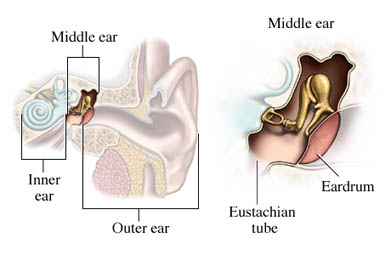

Overview

Package includes:

Days in hospital : 2 to 3 Days (For patient and one attendant)

Days in hotel : 6 Days (For patient and one attendant)

Room type in hospital : Shared

Room type in hotel : Private

Hotel category: Standard

Value added benefits of the Tympanoplasty: